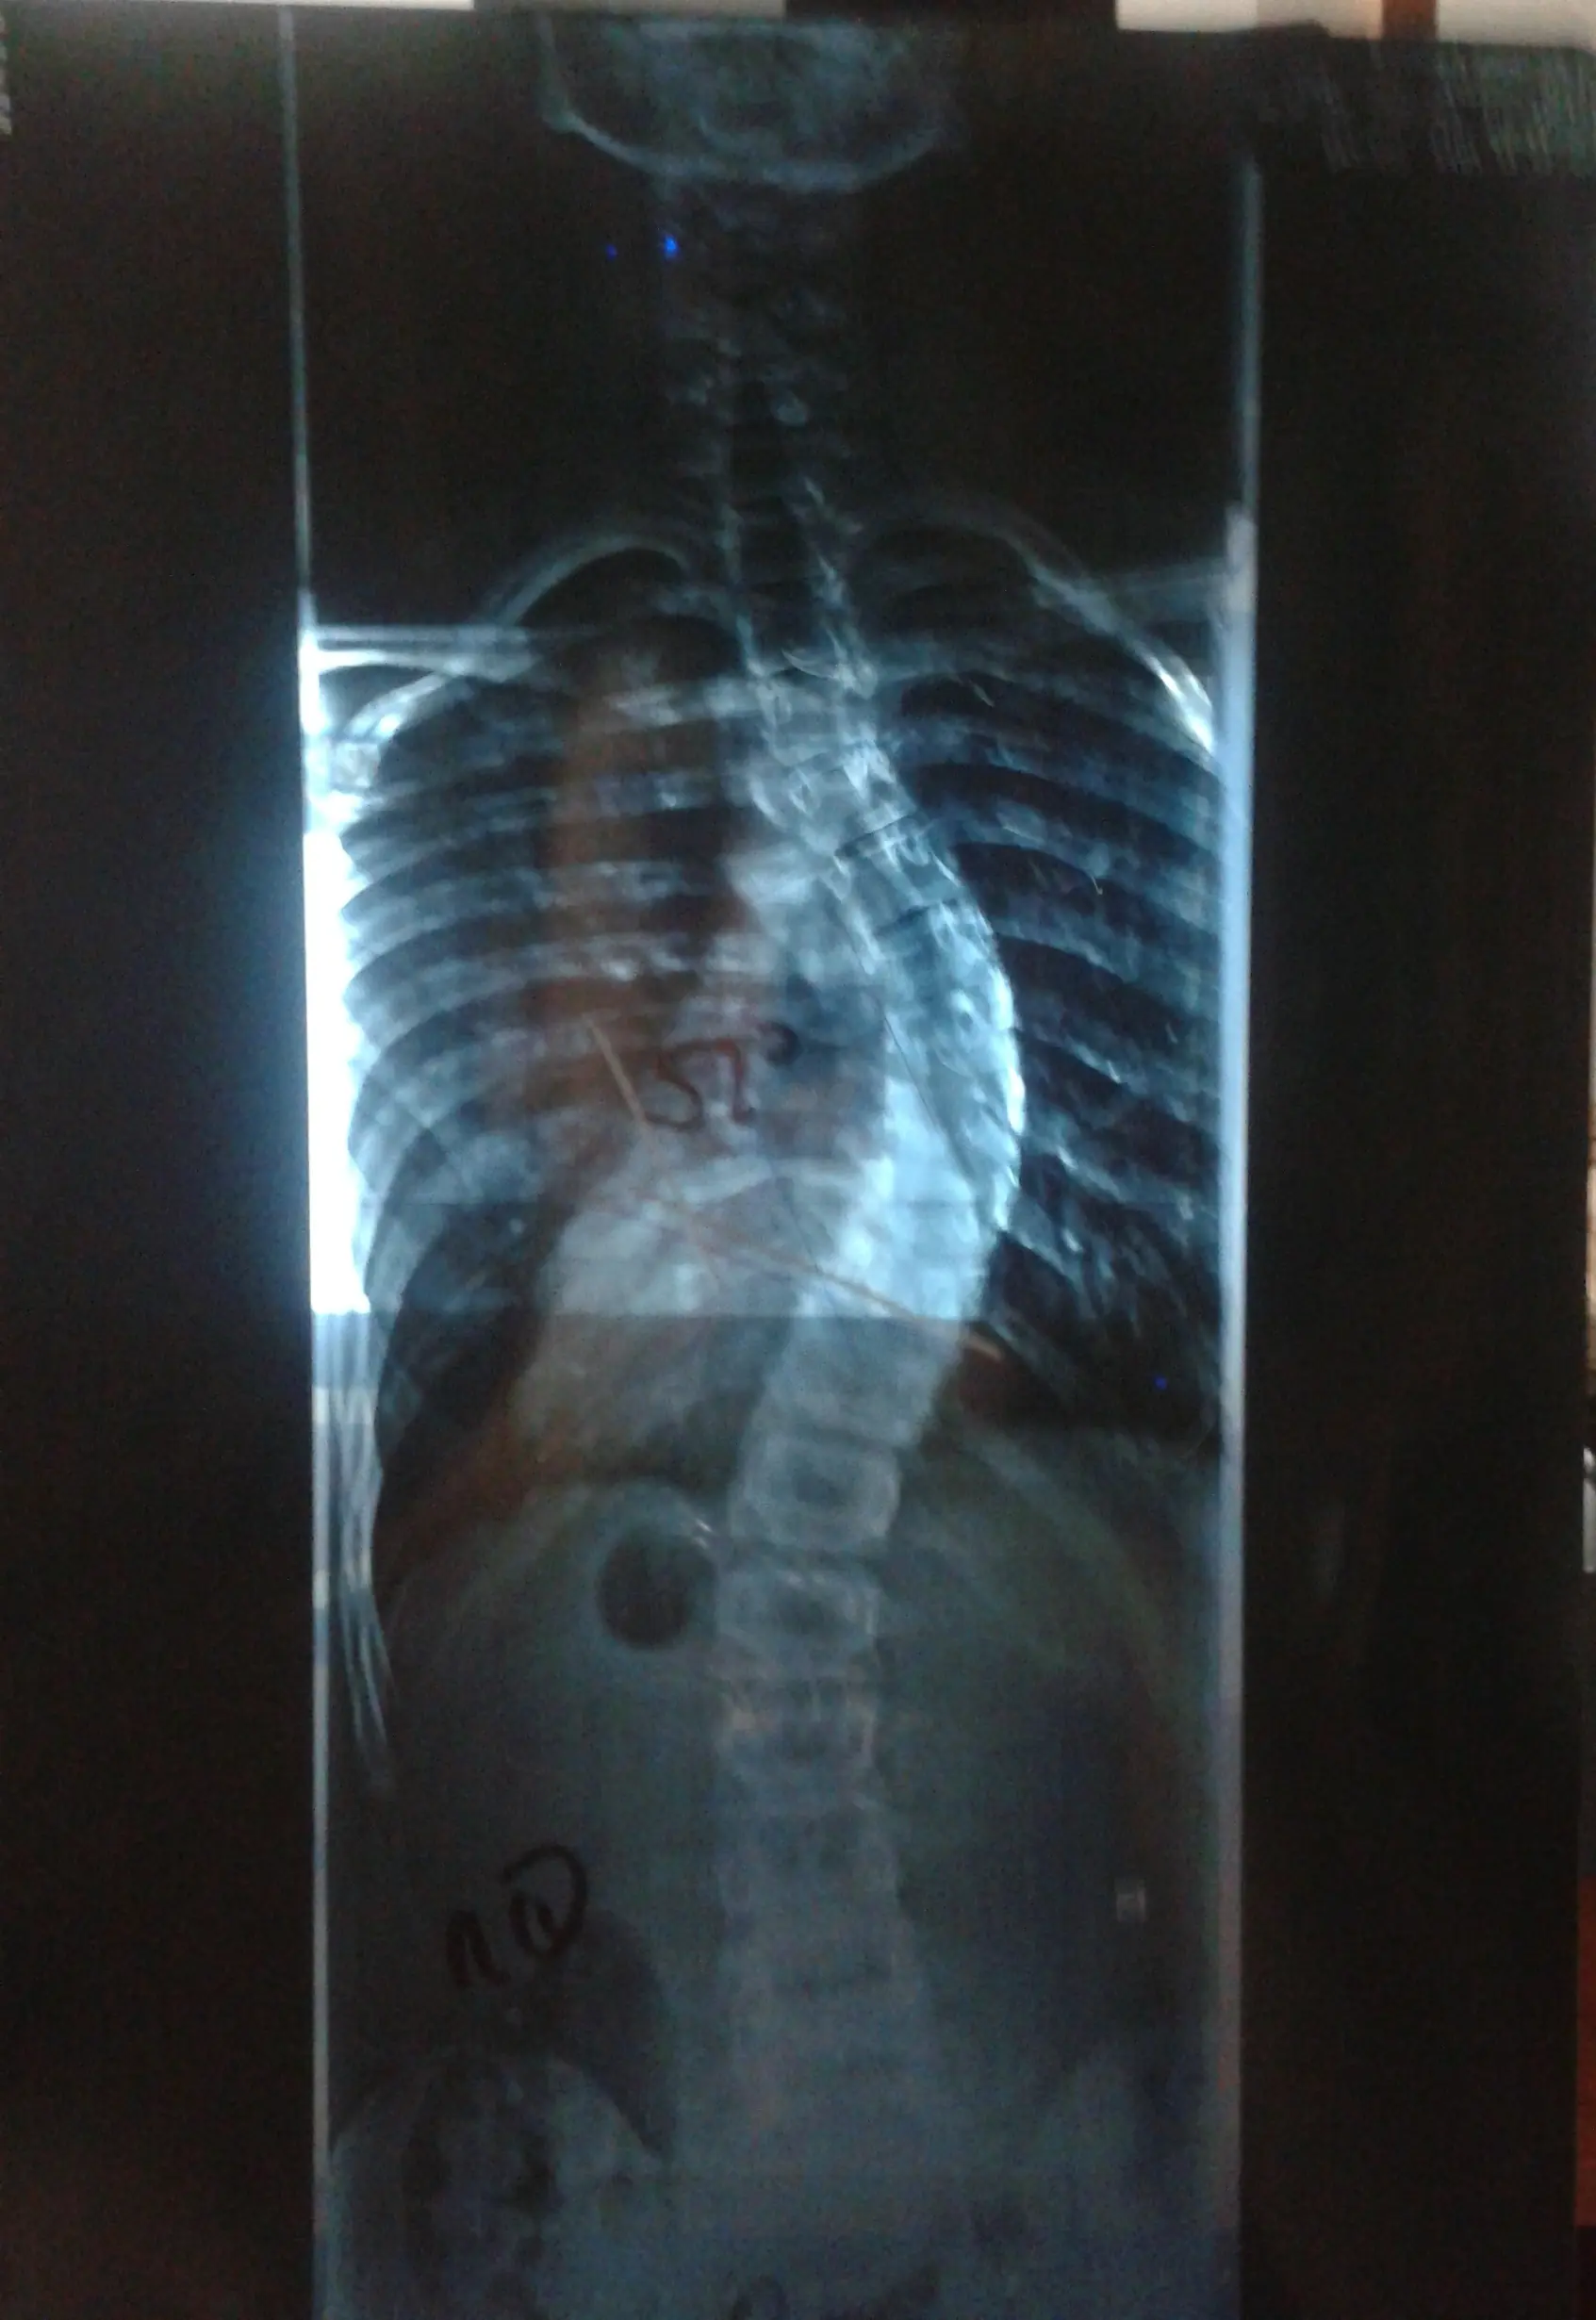

Pero el médico estaba en lo cierto, en 6 meses mi columna aumentó de 38º hacia 52º, quedando de esta manera:

Esa consulta fue los primeros dias de Febrero, desde ese día no pare de hacerme resonancias etc y revisiones que necesita el cirujano para operar. No se bien como consiste la operacion de la escoliosis, ni tampoco quiero enterarme bien, los primeros dias lloraba como un put*, pensaba en que me podia quedar paralitico, pero el cirujano me tranquilizo muchisimo.. Y ahora estoy tranquilo esperando el día, el 3 de Abril voy a ser internado en el instituto médico platense y el 4 de Abril seré operado, en una semana me voy del hospital y hasta Abril de 2015 no puedo volver a jugar al fútbol, algo muy doloroso para mí.